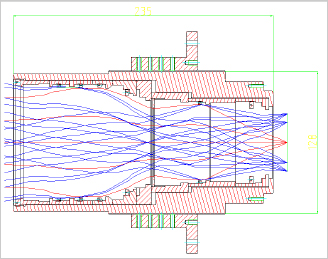

- Lens Shape